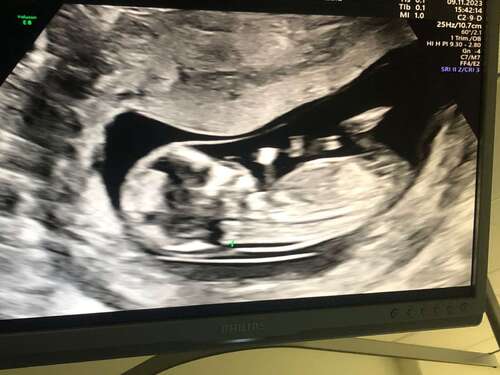

馃┓馃┑ wat denken julie

Hier zit helaas het beentje voor. Heb je meer foto鈥檚?